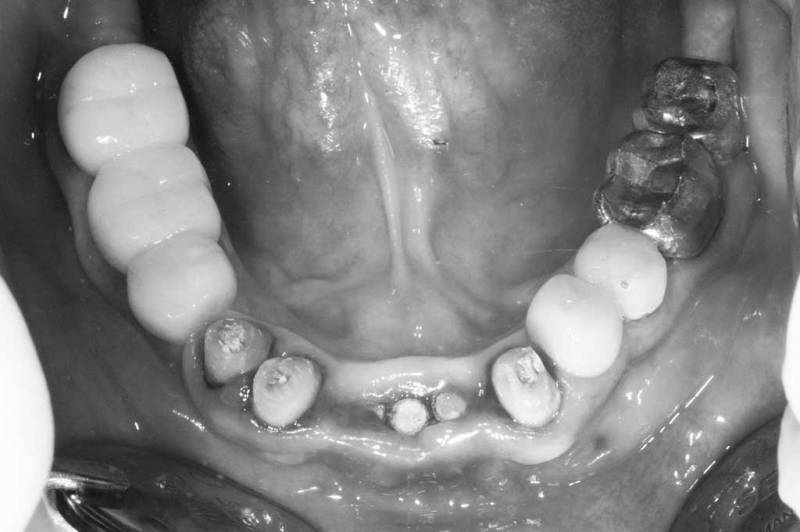

骨脊增厚術案例

案例1

骨脊增厚術術前

骨脊增厚術術中

骨脊增厚術術後

案例2